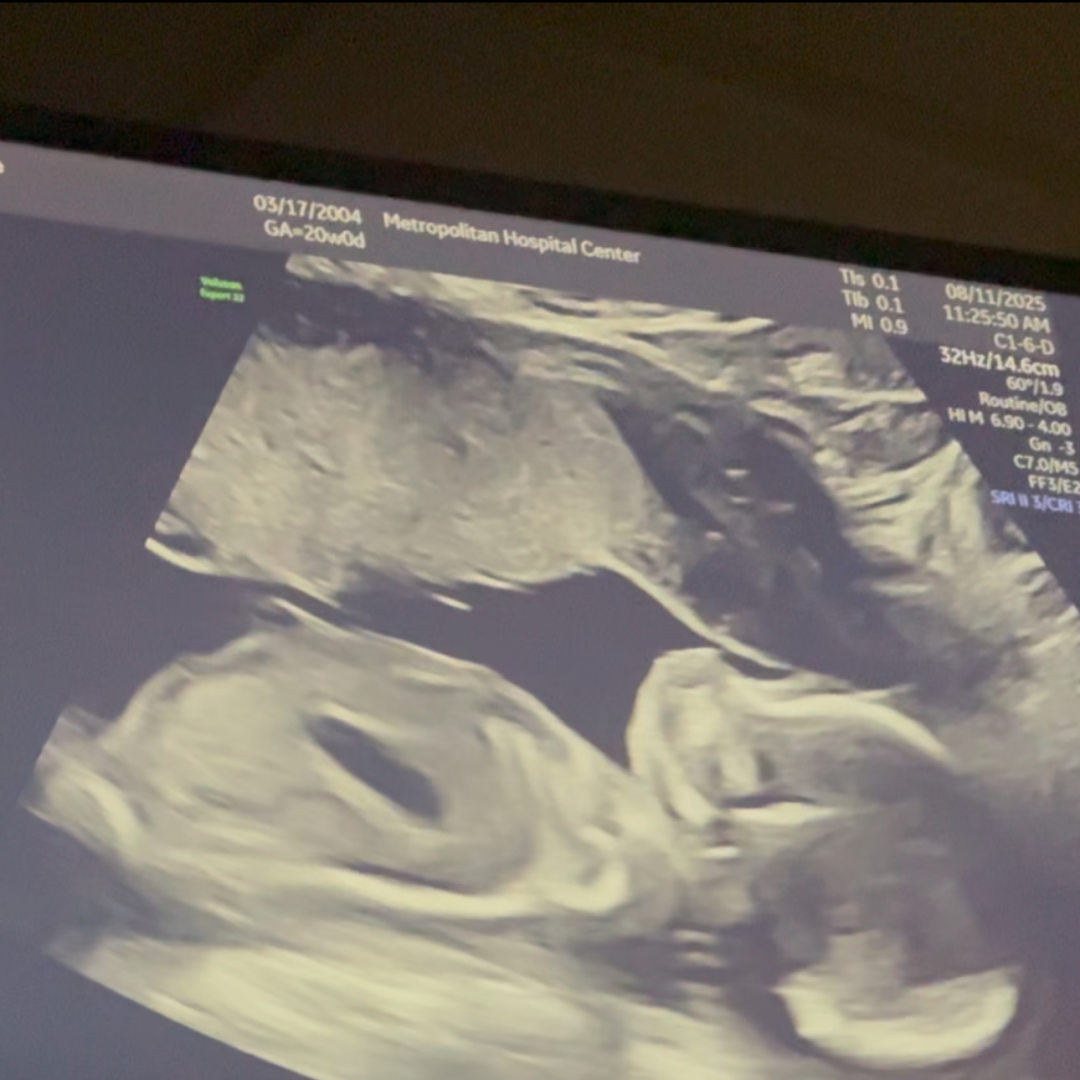

Photo shared by JAMIE for their Babylist baby registry.